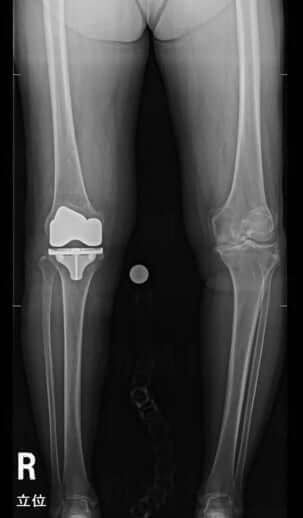

1枚目/5枚中

ライフ週刊新潮 2021年11月18日号掲載

屈指の経験を誇る水島医師